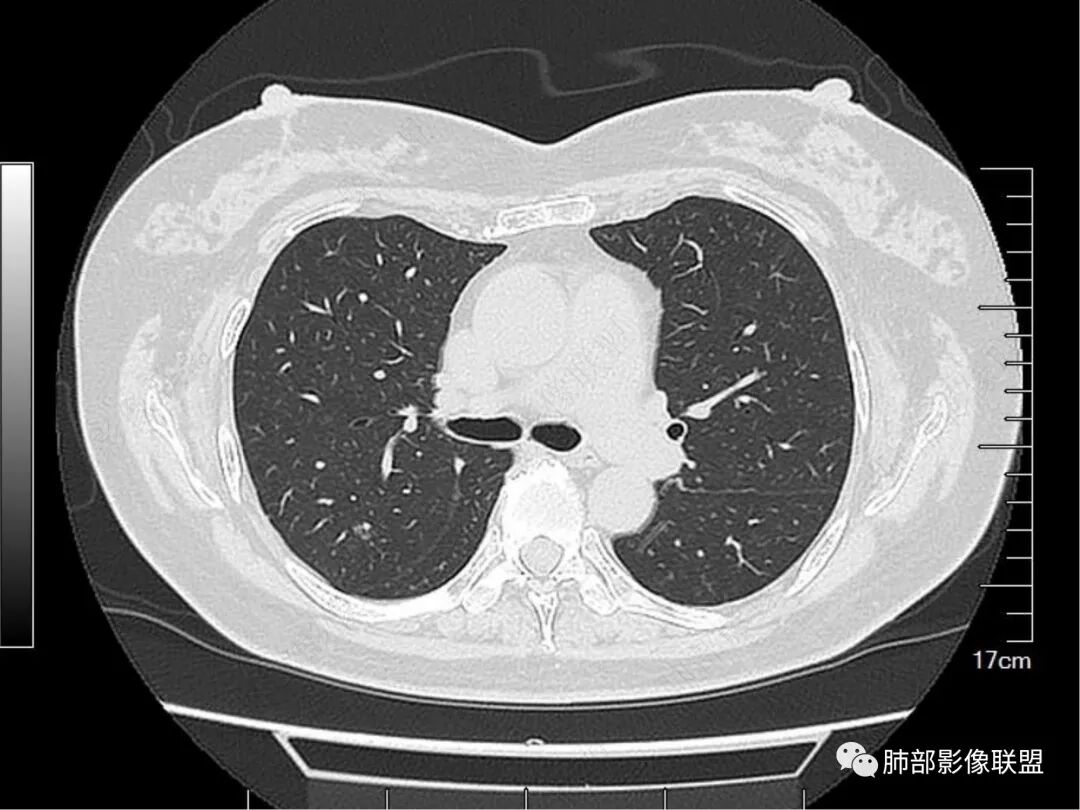

看完支气管我们继续看这个次级肺小叶的背景。

这里几乎是病灶的最上缘。明显是有丝丝拉拉的不干净的背景,与周围正常组织比较,很明确。

较中央的区域。明确的细网格,多发的。

这个细网格可以是什么引起呢?

1.血管因素,增粗的血管可以;

2.淋巴道因素,比如淋巴瘤、反应性淋巴增生;

3.结缔组织的内容增多,比如免疫性疾病相关造成的黏多糖或者什么复合物增多,或者是什么纤维增多;

4.很重要的一点,就是肺泡塌陷。邻近这种“隔”的肺泡塌陷,加上原有“隔”的背景,形成了这种增粗的表现。

请大家仔细观察这个条索,与胸膜相连,局部结节感。这个大概率是小叶间小静脉的走行。

这里有个特点,是偏侧的,不是reid's小叶 的一圈“隔”都增厚,是局限性的。这种增厚,什么原因可以引起呢?比如:血管的问题,里面有肿瘤。比如淋巴道的问题,有癌淋,或者有间质纤维的不规则增生。

请仔细观察病灶周围情况,比如临近血管、临近胸膜。有个特点,胸膜牵拉并不明显,邻近血管走行还算正常。

这里,可以佐证了。假如支气管扩张是收缩力引起的,而且支气管扩张如此明显,它周围的组织不会一丁点表现没有,离胸膜如此的近,竟然一点牵拉的意思都没有。

总结一下病变表现:病变区肺小叶背景不干净。整体位于单个次级肺小叶内,围绕小叶中心结构,部分局限于reid小叶的病变。支气管的显影,是肺泡填充为主要因素,收缩力可以有,但比较轻,或者无收缩力。小叶间小静脉存在增粗或者相应走行区存在局限性的淋巴道病变。